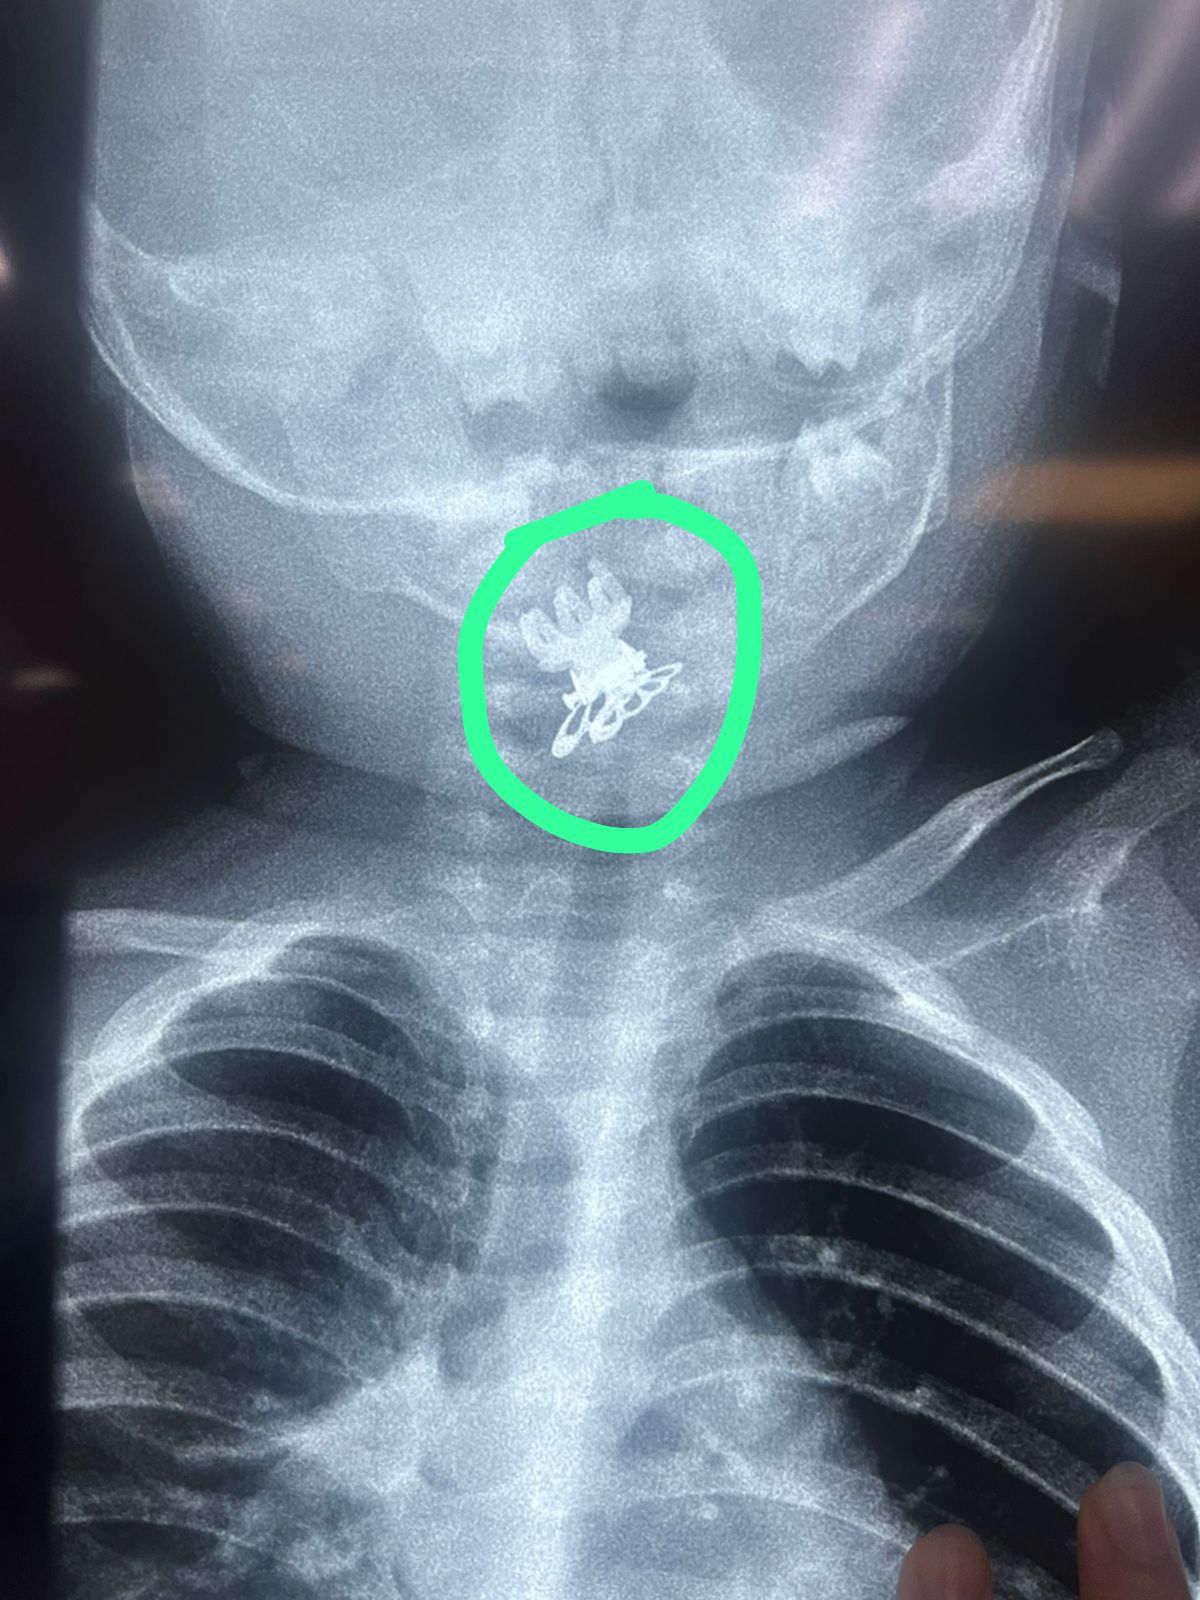

النجف: إستخراج قراصة شعر من مجرى تنفس طفلة

تمكن فريق طبي في مدينة الصدر الطبية بمحافظة النجف، من إنقاذ حياة طفلة تبلغ من العمر سنة ونصف السنة، بعد تعرضها لحالة اختناق شديدة نتيجة ابتلاعها مشبك شعر (قراصة) استقر في مجرى التنفس. وقالت الطبيبة الاختصاص في جراحة الأنف والأذن والحنجرة فرقان حميد محمد في بيان تلقته (الزمان) أمس إن (الطفلة أُدخلت إلى صالة عمليات الطوارئ وهي تعاني من اختناق وسعال شديدين، وعلى الفور تم إجراء الفحوصات والأشعة اللازمة التي أظهرت وجود جسم غريب في مدخل المجرى التنفسي). وأضافت إن (فريقاً طبياً برئاستها وبمشاركة الأطباء المقيمين الأقدمين وفريق التخدير والتمريض باشر بإجراء عملية دقيقة باستخدام الناظور، تم خلالها استخراج مشبك الشعر بنجاح ودون تسجيل مضاعفات). مؤكدة إن (الطفلة خرجت من العملية وهي بحالة صحية مستقرة بعد تحسن وضعها العام) وأشادت محمد (بجهود الفريق الطبي والتنسيق العالي الذي أسهم في إنقاذ حياة الطفلة). ولفتت إلى (أهمية التدخل السريع في مثل هذه الحالات الحرجة).